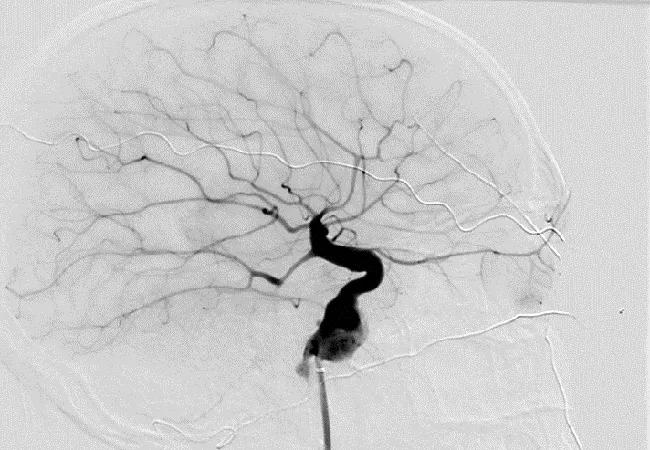

image of human brain with an intracranial aneurysm

Researchers at Cleveland Clinic have identified an apparent increased risk for intracranial aneurysm (IA) among people with Marfan syndrome in the largest review of IA in this population reported to date. The retrospective study was published in the Journal of Vascular Surgery (2023;76[3]:633-637).